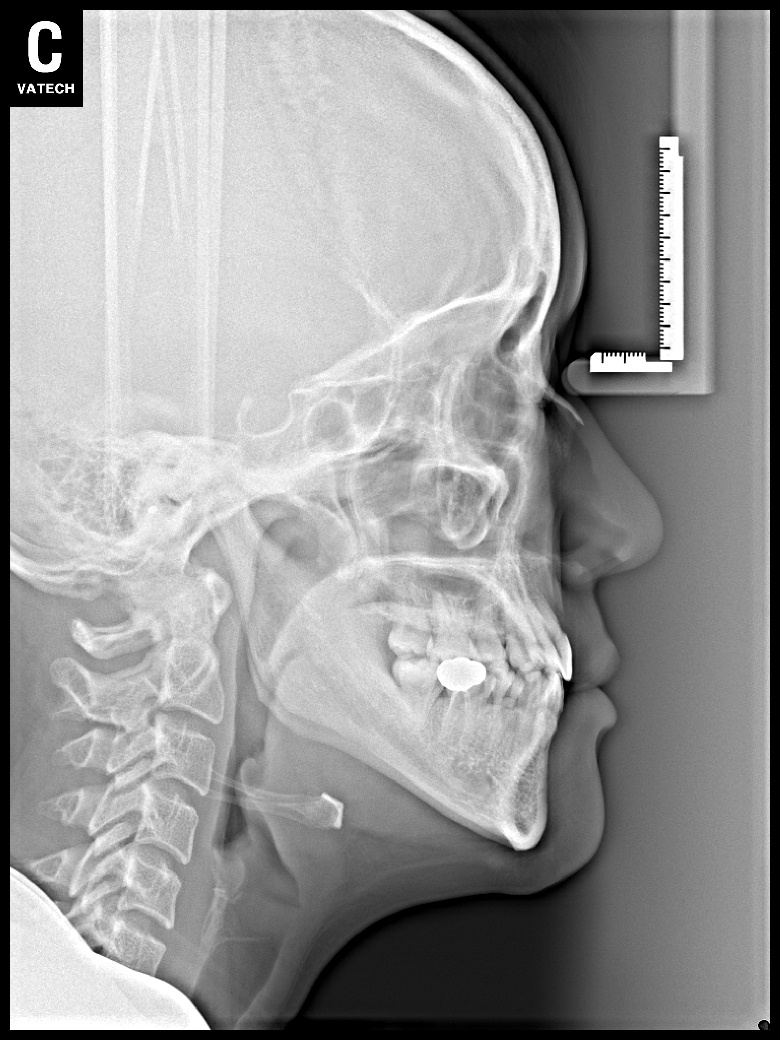

치료 전 사진입니다.